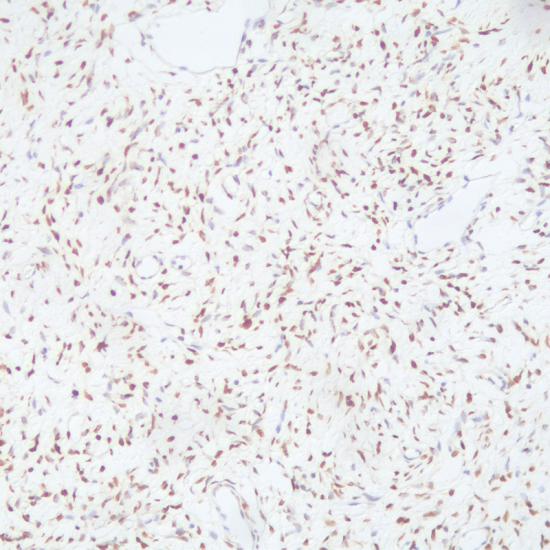

STAT6抗體試劑(免疫組織化學(xué)法) 閩廈械備20190119號

• 陽性部位:

細(xì)胞核

• 陽性對照:

孤立性纖維瘤

STAT6是信號轉(zhuǎn)導(dǎo)和轉(zhuǎn)錄活化因子家族(STAT)的一員,大多數(shù)孤立性纖維瘤在染色體12q13位置存在特異性的NAB2-STAT6融合基因過表達(dá),無活性的STAT6以二聚體的形式存在胞漿中。在免疫組織化學(xué)檢測中,STAT6抗體彌漫細(xì)胞核表達(dá)與腫瘤內(nèi)存在NAB2-STAT6融合基因具有高度的一致性,STAT6可作為孤立性纖維瘤的一個特異分子標(biāo)志物。